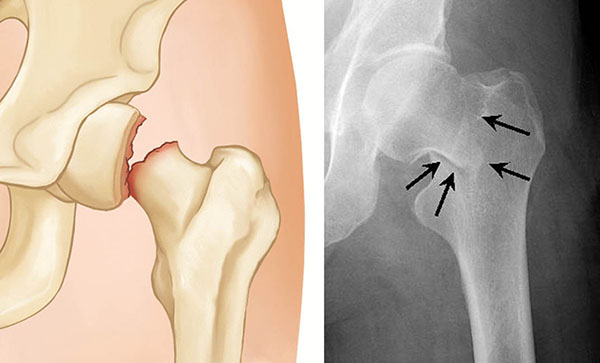

Hip Labral Tears

Damage to cartilage causing hip pain and clicking.

Effective hip and pelvis treatment begins with an accurate diagnosis. Our specialists carry out a detailed clinical examination, assessing movement, strength, alignment, and areas of tenderness. When required, imaging tests such as X rays or MRI scans may be advised to better understand the joint structure and identify the root cause of pain.

Diagnosis includes a detailed clinical examination and may involve imaging tests such as X-rays, MRI, or CT scans to identify the exact cause.